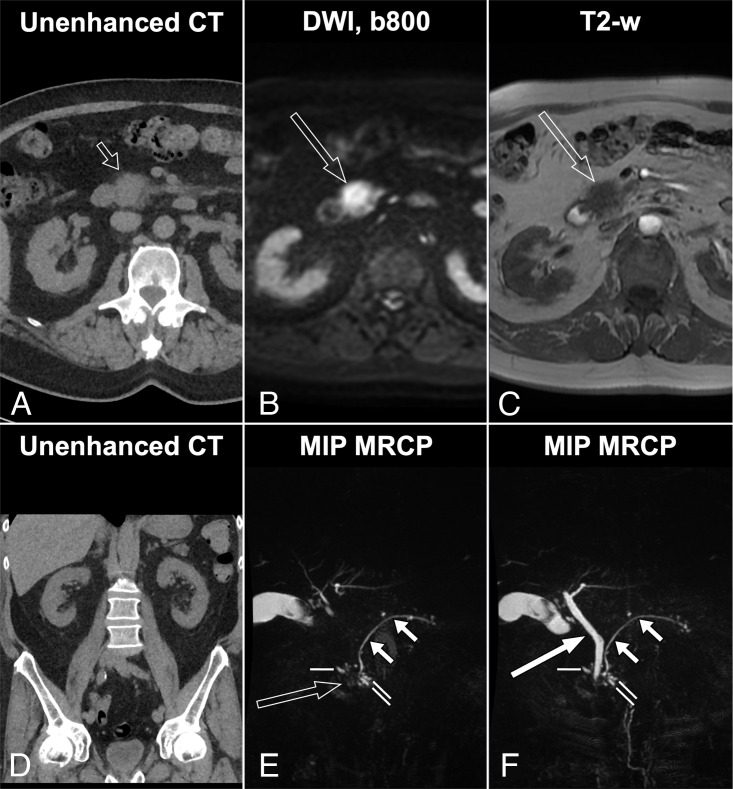

Abstract Image